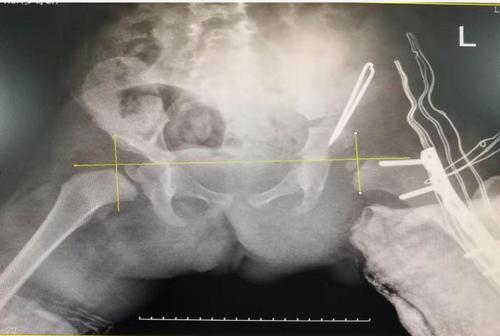

术后